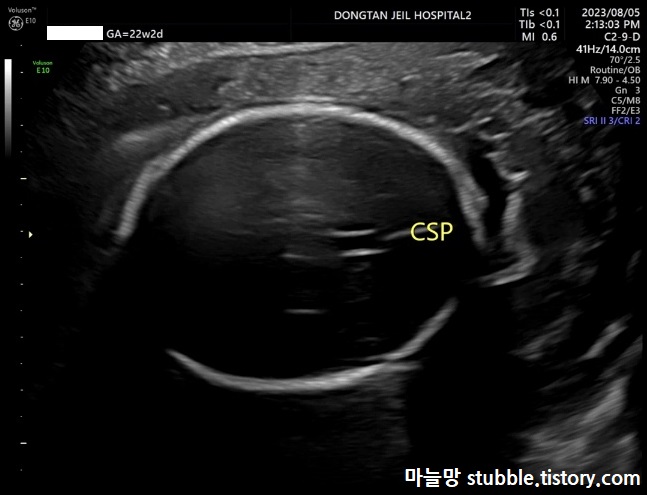

12. 태아의 뇌량 (CSP)